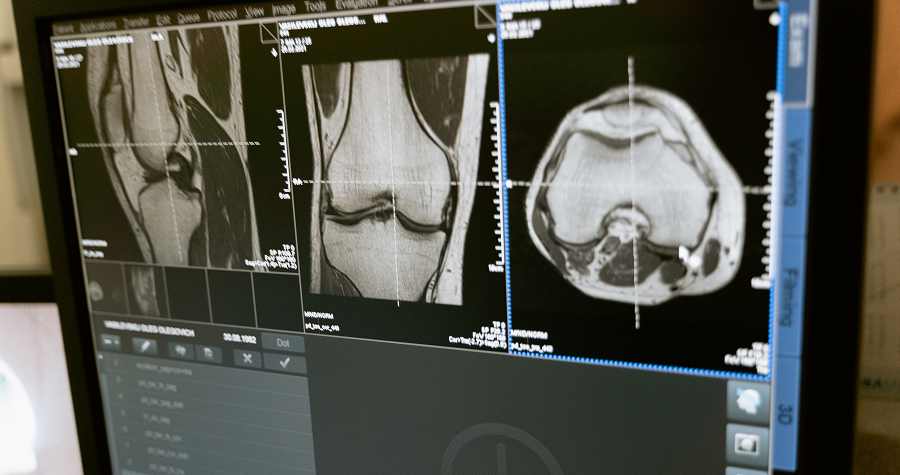

의료영상 저장 전송 시스템 (PACS, Picture Archiving and Communication System)

이러한 병원의 관리 업무 전산화를 넘어 진료 업무의 전산화에 대한 요구는 여기서 그치지 않고, 이미 선진국의 여러 병원에 설치 운영되고 있는 PACS, Teleradiology 등에 대한 국내의 관심은 어느 때 보다도 높고 그 실현 가능성도 높아지고 있다. 그러나 많은 의사 또는 병원 시스템 담당자, 의료기 관련 업무 종사자들의 이에 대한 이해가 부족하여 도입하고 싶은 시스템에 대해 지나친 환상을 갖거나 또는 지나친 회의주의로 인해 국내의 시스템 도입 사례나 운영 수준이 매우 낮음을 인정할 수 밖에 없다. 대형 병원에 도입된 PACS의 사례를 통해 그 시스템의 장점과 단점 등이 국내에 알려지면서 PACS 도입을 하고자 하는 국내 병원의 수가 점점 늘어가는 추세이다.

CT, MRI, US

원래 CT, MR Scanner 장비는 영상을 생성할 때부터 가로 512 세로 512의 해상도(또는 256 x 256, 128 x 128)로 영상을 구성 한다. 즉 영상 발생 방법이 디지털화 되어 있어 초기부터 일정 크기의 영상을 제공하므로 이를 화면에 표시하는 방법 역시 원래의 시스템과 같은 해상도를 사용 한다. 물론 1장의 Slice를 말한다. 반면 US 장비의 경우에는 아날로그 신호를 512 x 512 크기로 디지털화하여 사용 한다. 이때에는 별도의 장비가 필요하다.

CT, MR

이 경우에는 원래 영상이 디지털화 되어 생성되므로 상당히 높은 분해능을 가진다. 정교한 진료에 이용하는 이유가 바로 여기에 있다. 보통 12-16Bit를 사용하며 이는 장비에 따라 다르게 나타난다. 다만 장비에 붙어 있는 모니터에는 이 영역에서 일부분 즉 8Bit만을 사용하여 화면에 보여주며 필름화 할 때도 8Bit를 사용 한다. 잘 이해가 안될지 모르지만 영상의 원래 자료는 12Bit 혹은 16Bit로 디스크에 저장되어 있으나 이 저장된 영상을 화면에 보여 줄 때는 촬영 목적에 맞도록 보고자 하는 부위에 가장 적절한 8Bit를 사용한다는 것이다. 그 결과 같은 자료라도 보고자하는 부위에 따라 여러 가지 밝기의 영상을 얻을 수 있는데 이 8Bit 사용 영역을 Window라고 부르며 이렇게 보기 좋은 상태로 사용 영역을 조절하는 것을 Windowing 또는 Window Leveling 이라고 한다. 물론 PACS에서도 같은 기능의 분해능을 제공 한다. 이러한 Window Leveling 기능은 X-ray에서는 볼 수 없는 기능이며 PACS의 가장 유용한 기능이기도 하다.